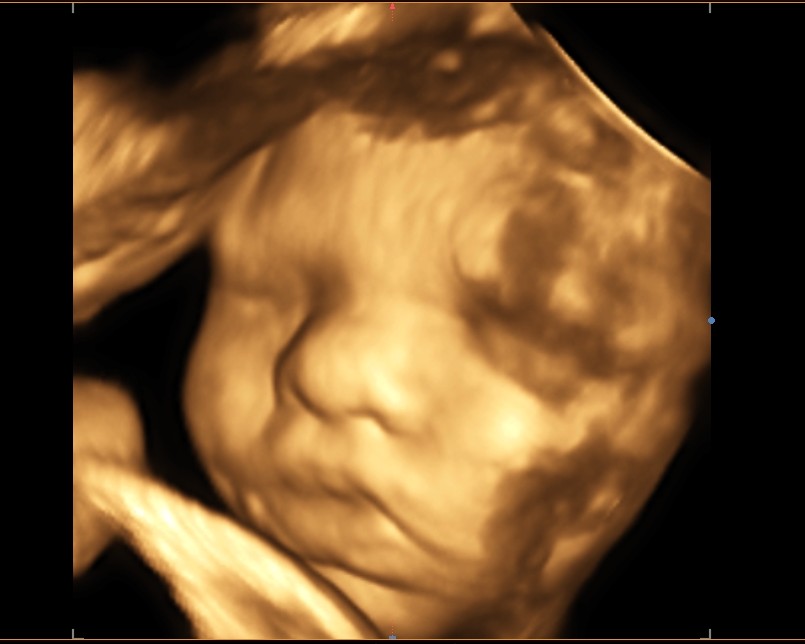

Ultrazvuky umožňují i dopplerovská měření a 3D-4D zobrazení

• Provádíme 3D-4D zobrazení (vzhledem k časové náročnosti si pacientky objednáváme mimo ordinační dobu).